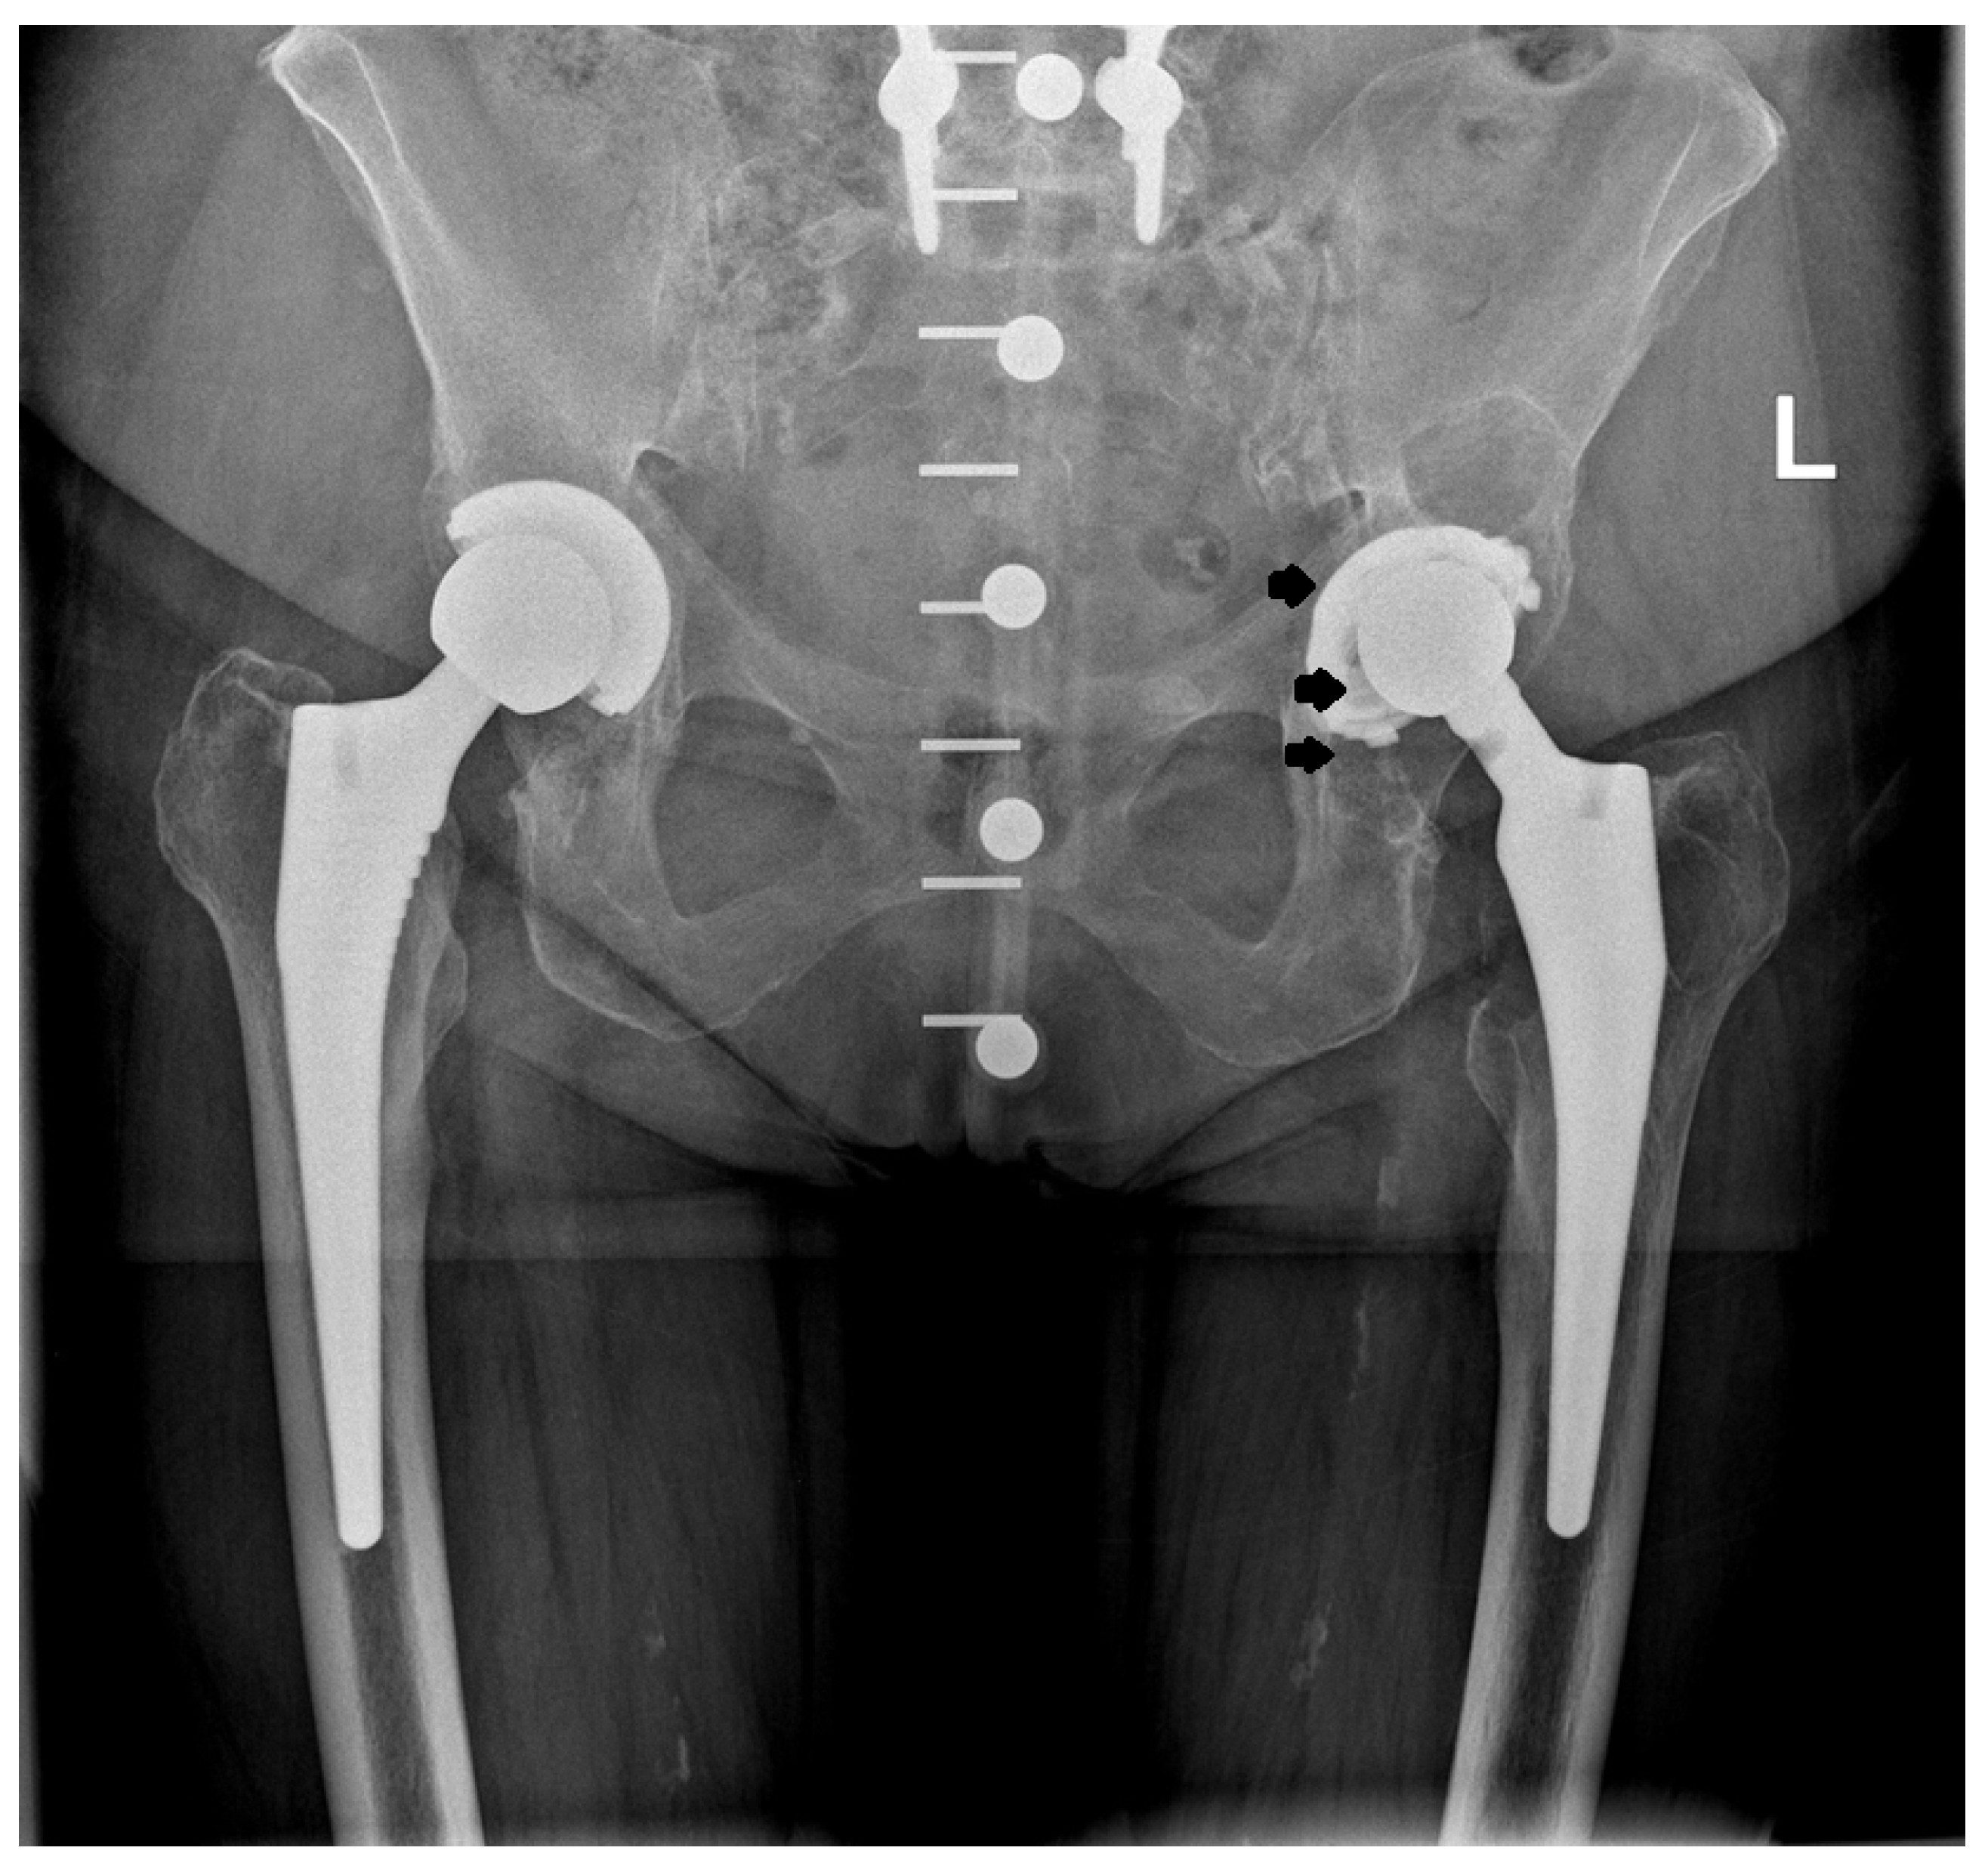

2.2. Design of the L-Cup Acetabular Component

2.4. Acetabular Implantation